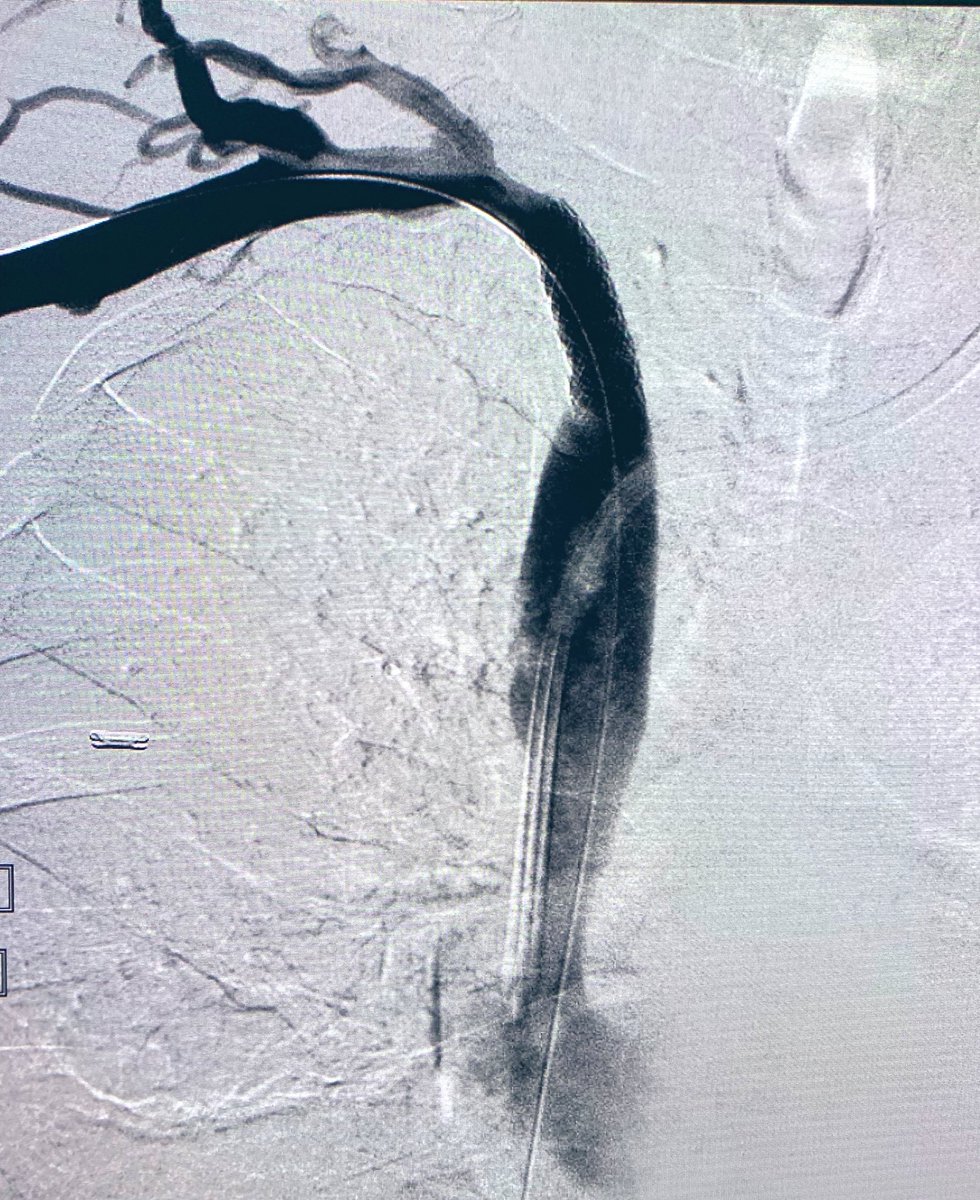

Last case of 2019. Successful

#recanalisation of chronic#splenicvein#occlusion using#transhepatic approach.#portalvein and#SMV reconstructed for#palliation#pancreaticcancer. Wish everyone happy 2020.#irad@SIRspecialists@SIR_ECS@SIRRFS@JVIRmedia@CVIR_Journalpic.twitter.com/Lgma0lTJUd